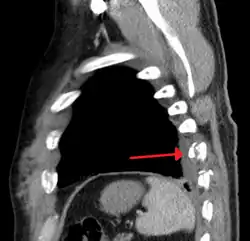

Plain X-rays often pick up displaced fractures but often miss undisplaced fractures.[13] CT scanning is generally able to pick up both types of fractures.[13]

Two broken ribs as seen on parasagittal CT